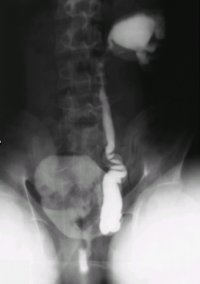

Bei dem Jugendlichen fand sich eine Doppelniere links mit hydronephrotischen Doppelnierenanteil bei VUR III.° in den unteren Anteil. Es bestand ein rezidivierender fieberhafter Harnwegsinfekt. Die Sonographie ergab eine unauffällige rechte Niere, links eine Doppelniere mit regelrechtem oberen und einem hydronephrotischen unteren Nierenanteil (Abbildung 7). Die Harnblase war unauffällig. Im Ausscheidungsurogramm fand sich eine Doppelniere links mit dilatiertem unteren Nierenanteil bei Ureter duplex (Abbildung 8a). Der Kontrastmittelabstrom aus dem unteren Nierenanteil war verzögert (Abbildung 8b). Im Zystogramm fand sich ein Vesikoureteraler Reflux (III.°) in das untere Nierenhohlraumsystem. In der Zystoskopie zeigte sich ein Golflochostium des fehleinmündenden unteren Harnleiters links. Die Nierensequenzszintigraphie ergab in der Gesamtclearence 288 ml/min (NB: > 255 ml/min) (Abbildung 8c).

Bei den rezidivierenden Harnwegsinfekten, den morphologischen Veränderungen der linken Niere und dem bestehenden Vesikoureteralen Reflux in den unteren Nierenanteil links führten wir eine Heminephrektomie des unteren Doppelnierenanteils durch.